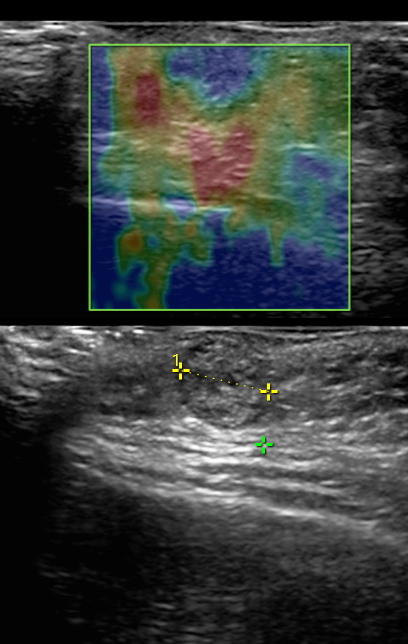

Esta elasticidad o rigidez de los tejidos se representa en un mapa de colores predeterminado por el operador, siendo lo mas frecuente azul para tejidos rígidos y amarillo, verde y rojo para tejidos con alta elasticidad.

En el caso de la mama y la tiroides, la elastografía se ha vuelto invaluable. Cuando se trata de identificar lesiones o anomalías en estos órganos, la capacidad de evaluar la elasticidad de los tejidos puede marcar la diferencia. Las lesiones malignas o anómalas a menudo tienen una textura diferente a la de los tejidos sanos, y la elastografía nos permite detectar esas sutiles diferencias.